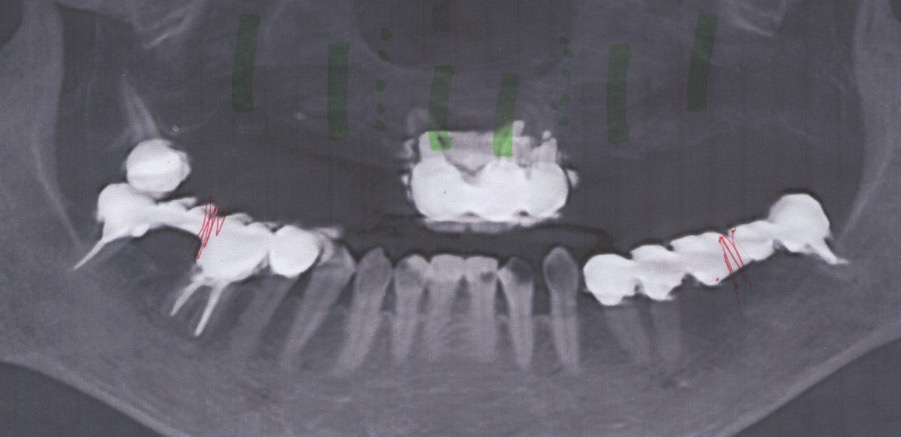

- 10年前から他の歯科医院にて入れ歯治療を受けたが、見た目が良くない・噛めないと・喋りにくいとのことで再治療を希望された。アングルクラスⅢであった。左右上奥歯がない。

- 上顎左右側にインプラントを8本し、

- 入れ歯+オールセラミックのボーンアンカーブリッジにて被せ物を行なった。

- 下顎臼歯に3本のインプラントを入れ、オールセラミッククランにて被せ物を行なった。